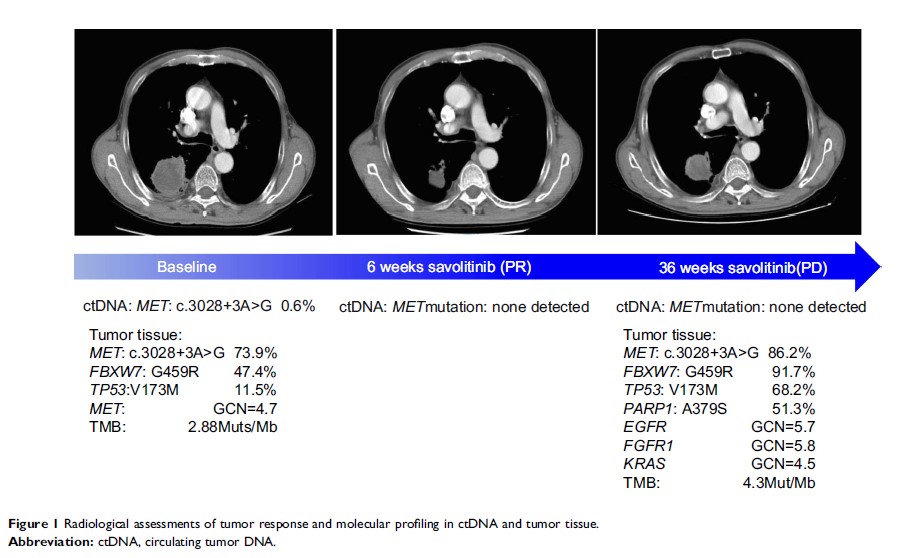

Case Report

伴有 MET 外显子 14 跳跃突变的肺肉瘤样癌患者对沃利替尼的反应和获得性耐药:病例报告